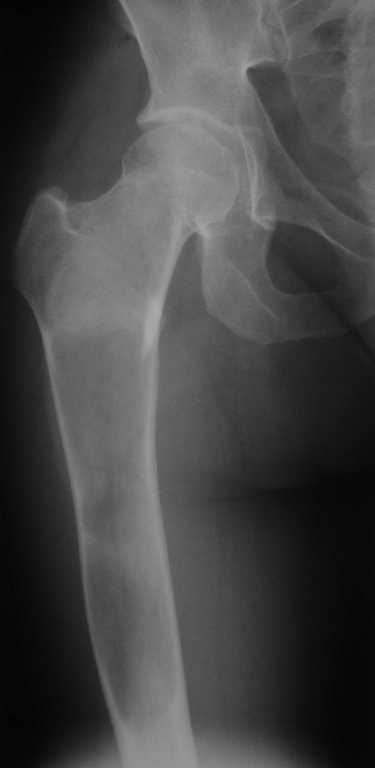

Уважаемые коллеги! В клинику поступила молодая женщина 35 лет с жалобами на интенсивные боли в области правого бедра, носят спонтанный характер, имеются "ночные" боли.

Движения в правом тазобедренном суставе в полном объёме, практически безболезненные. По результатам x-ray диагностики выявлен патологический очаг, занимающий весь проксимальный отдел и 2/3 диафиза правой бедренной кости. Другие трубчатые кости верхних и нижних конечностей - без очагов поражения.

Имеется небольшой (1,5х2,5 см) очаг в крыле правой подвздошной кости.

По результатам трепанобиопсии проксимального отдела правой бедренной кости - фиброзная строма и костные балки, без атипии.